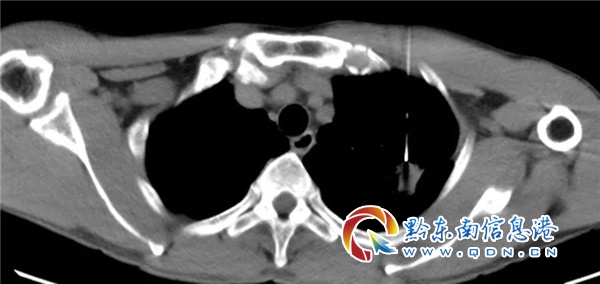

患者袁某某,男,51歲,貴州天柱縣人。因“咳嗽、胸悶、胸痛10天”入我院感染科。胸部CT:1.左上肺病灶(結核?肺Ca?直徑大小:2.1×1.7cm)伴周圍少許炎癥,鄰近胸膜增厚、粘連。右肺中葉結節;2.縱膈淋巴結顯示增多。建議:CT增強及穿刺活檢。遂轉入胸部腫瘤科,經彭杰博士接診后,考慮患者肺部腫瘤可能性大。并完善頭顱及腹部影像學檢查均未見明顯轉移灶,與患者及家屬充分溝通后,由彭杰博士行CT引導經皮肺穿刺活檢術。病理示:肺腺癌。初步診斷:左上肺腺癌并縱膈淋巴結轉移 (T2N2M0, ⅢA期)。

會議首先由彭杰博士介紹患者病情及相關影像、病理、實驗室檢查結果,接著南方醫院影像中心專家詳細解讀胸部增強CT結果,胸部縱膈淋巴結及胸膜侵犯均存疑,縱膈淋巴結偏向良性可能,建議PET-CT檢查。胸外科專家從外科角度對病人的病情進行分析,建議PET-CT或者E-BUS檢查,明確縱膈淋巴結轉移情況,胸膜是否累及不能排除,同時也提議可以考慮直接行胸腔鏡下肺癌根治術,根據術后結果安排是否輔助治療。腫瘤放療專家根據影像考慮胸膜侵犯不能確定,縱膈淋巴結轉移N2可能性大,提議完善PET-CT或者E-BUS檢查,如果為N2提議根治性同步放化療。最后經反復討論及與患者溝通:建議患者先行PET-CT檢查,明確腫瘤分期后按分期模式行外科手術或者同步放化療。患者及家屬表示經參會后對肺癌的治療有了更大的信心。